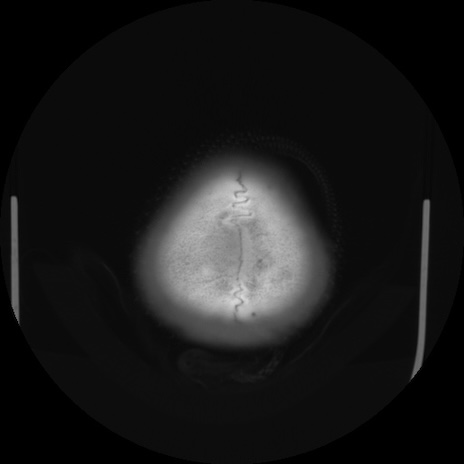

CT(矢状断像)